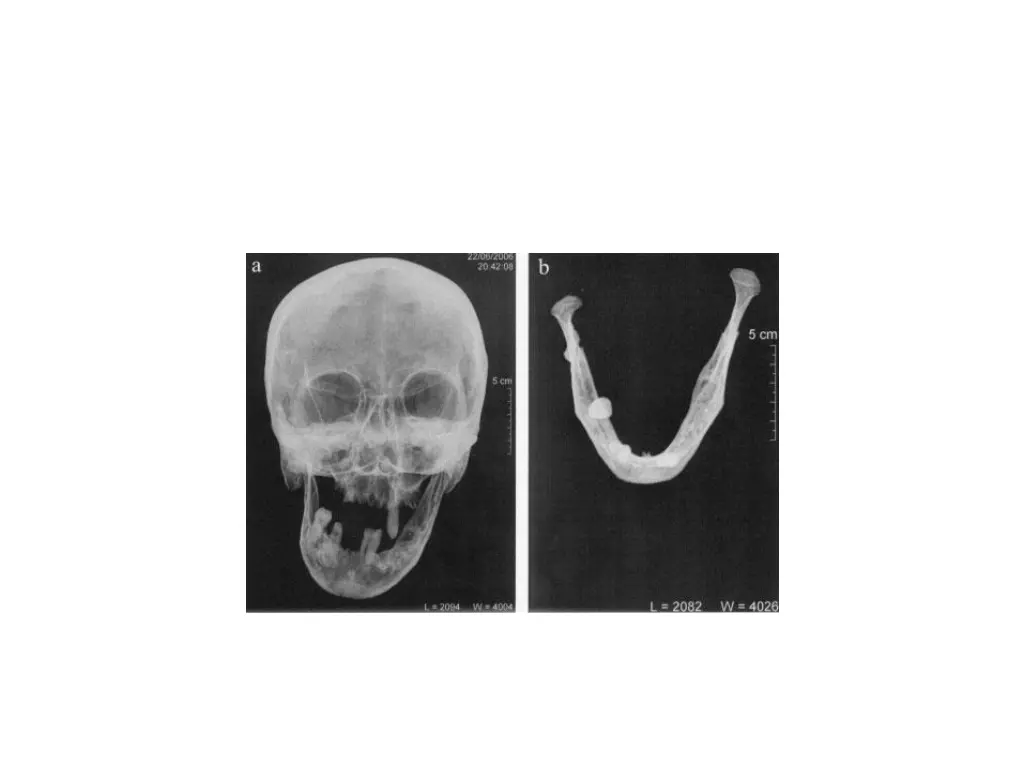

Computed tomography Indicated when information about 3 D shape and internal structure of osseous components of joint or if information regarding the surrounding soft tissues is required Image slices are made in both axial and coronal planes Reformat images are produced in sagittal planes and 3D Indications: to assess osseous deformities of jaws or surrounding structures

Indications Presence and extent of ankylosis and neoplasms Extent of bone involvement in some arthritis Imaging complex fractures Evaluating complications from use of polytetrafluoroethylene or silicon sheet implants such as erosions into middle cranial fossa and heterotopic bone growth